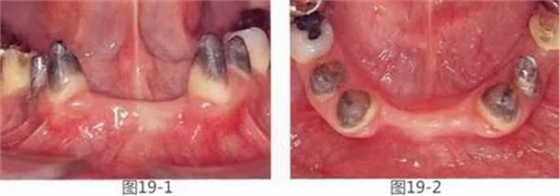

圖19-1 將左下1,2,右下1,2拔除后4個月的正面照。

圖19-2 同時期咬合面照。佩戴臨時修復(fù)體后,由于易滯留食物殘?jiān)磕诩t困難而感到不滿。